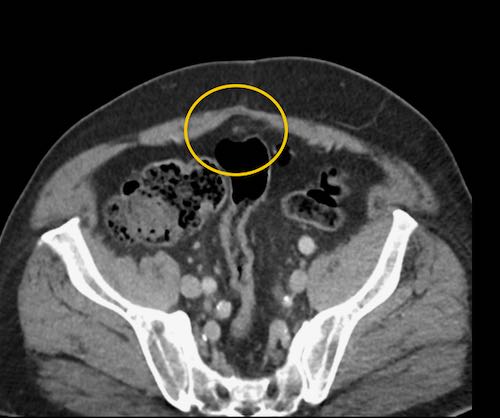

Cuộn xem ảnh CT

Ca lâm sàng 1

Cuộn qua các lát cắt.

Bạn có thể phát hiện tất cả các tổn thương cấy ghép phúc mạc không?

Bệnh nhân này đã được phẫu thuật và toàn bộ phúc mạc được ghi nhận phủ kín bởi các tổn thương u dạng kê.